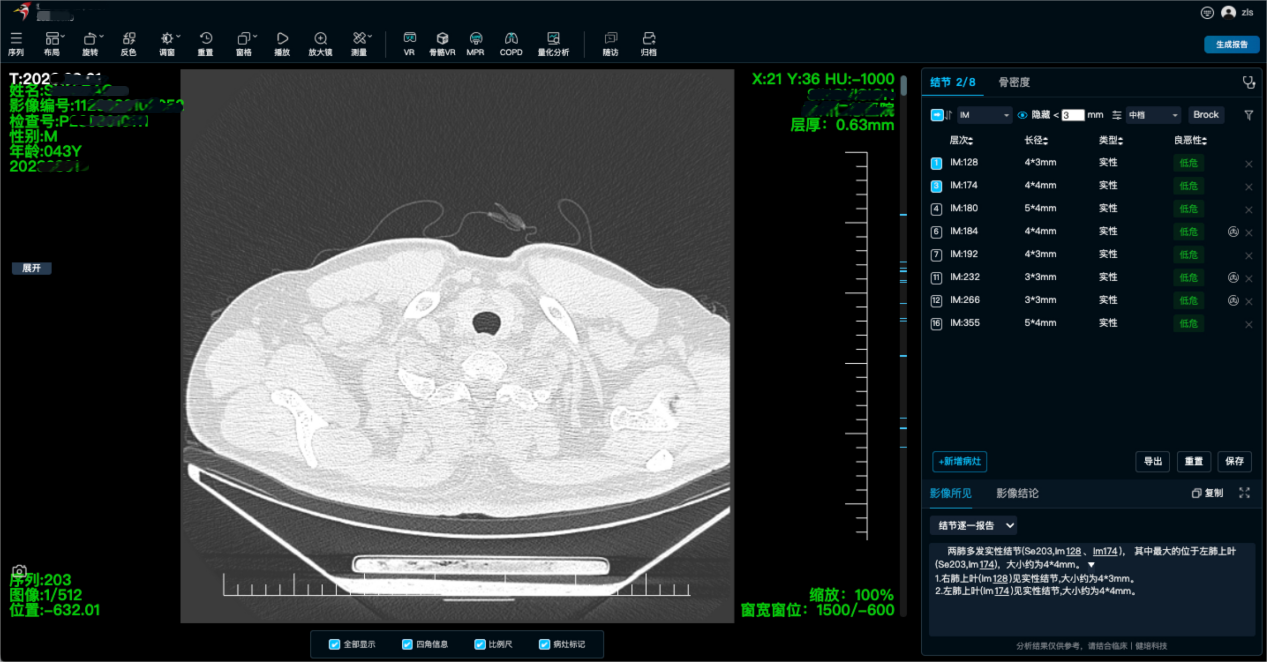

啄醫(yī)生能夠自動(dòng)對(duì)醫(yī)學(xué)影像進(jìn)行閱片和診斷,提供準(zhǔn)確的診斷結(jié)果和病灶信息,醫(yī)生可以根據(jù)啄醫(yī)生的診斷結(jié)果進(jìn)行進(jìn)一步的判斷和治療。覆蓋多種疾病類型,包括但不限于腫瘤、神經(jīng)、心腦血管、骨科、外科、體檢、急診、婦幼、質(zhì)控等場(chǎng)景為中心的AI精準(zhǔn)診斷,覆蓋全身部位、全影像模態(tài)及多元臨床場(chǎng)景。